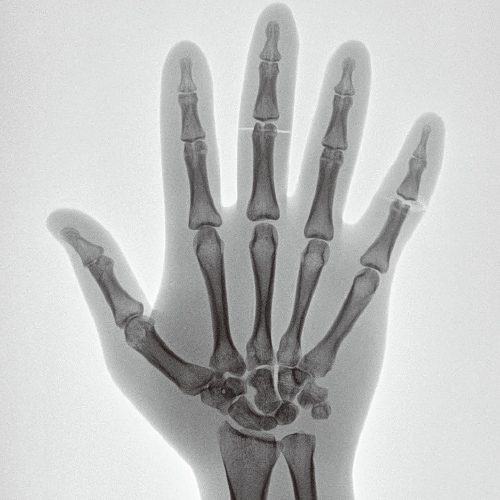

Edge enhancement

Improving procedural accuracy by enhancing the edges of bones, devices, and blood vessels without increasing radiation dose.

Original image

Low Enhancement image

High Enhancement image